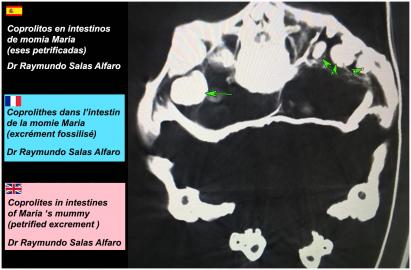

Planches (Dr José Rios de la Cruz) - Scanners (Dr Raymundo Salas Alfaro)

Scanners et radios de la grande "MARIA" de 168 cm

(cliquer sur les planches pour les agrandir)

Organes internes

Intestins, larynx, trachée, cavun.